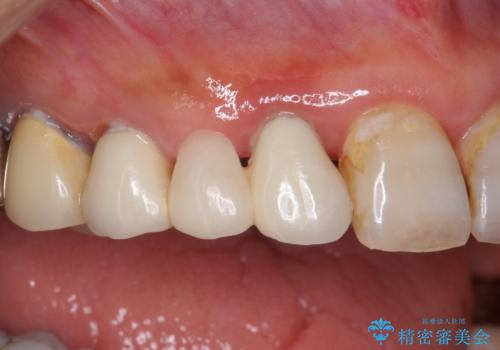

- 被せ物がかけてしまったことを主訴に来院された患者様です。

口腔内を精査したところ、右上のブリッジの内側(口蓋側)がかけており、下の前歯(右下1)には唇舌側に瘻孔を伴う大きな根尖病変ができていました。

右上のブリッジ(右上④3②)のやりかえと、下の前歯(右下1)の根管治療を行った後セラミッククラウンによる補綴治療を行いました。